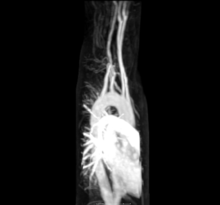

Aberrant right subclavian artery at angiography.